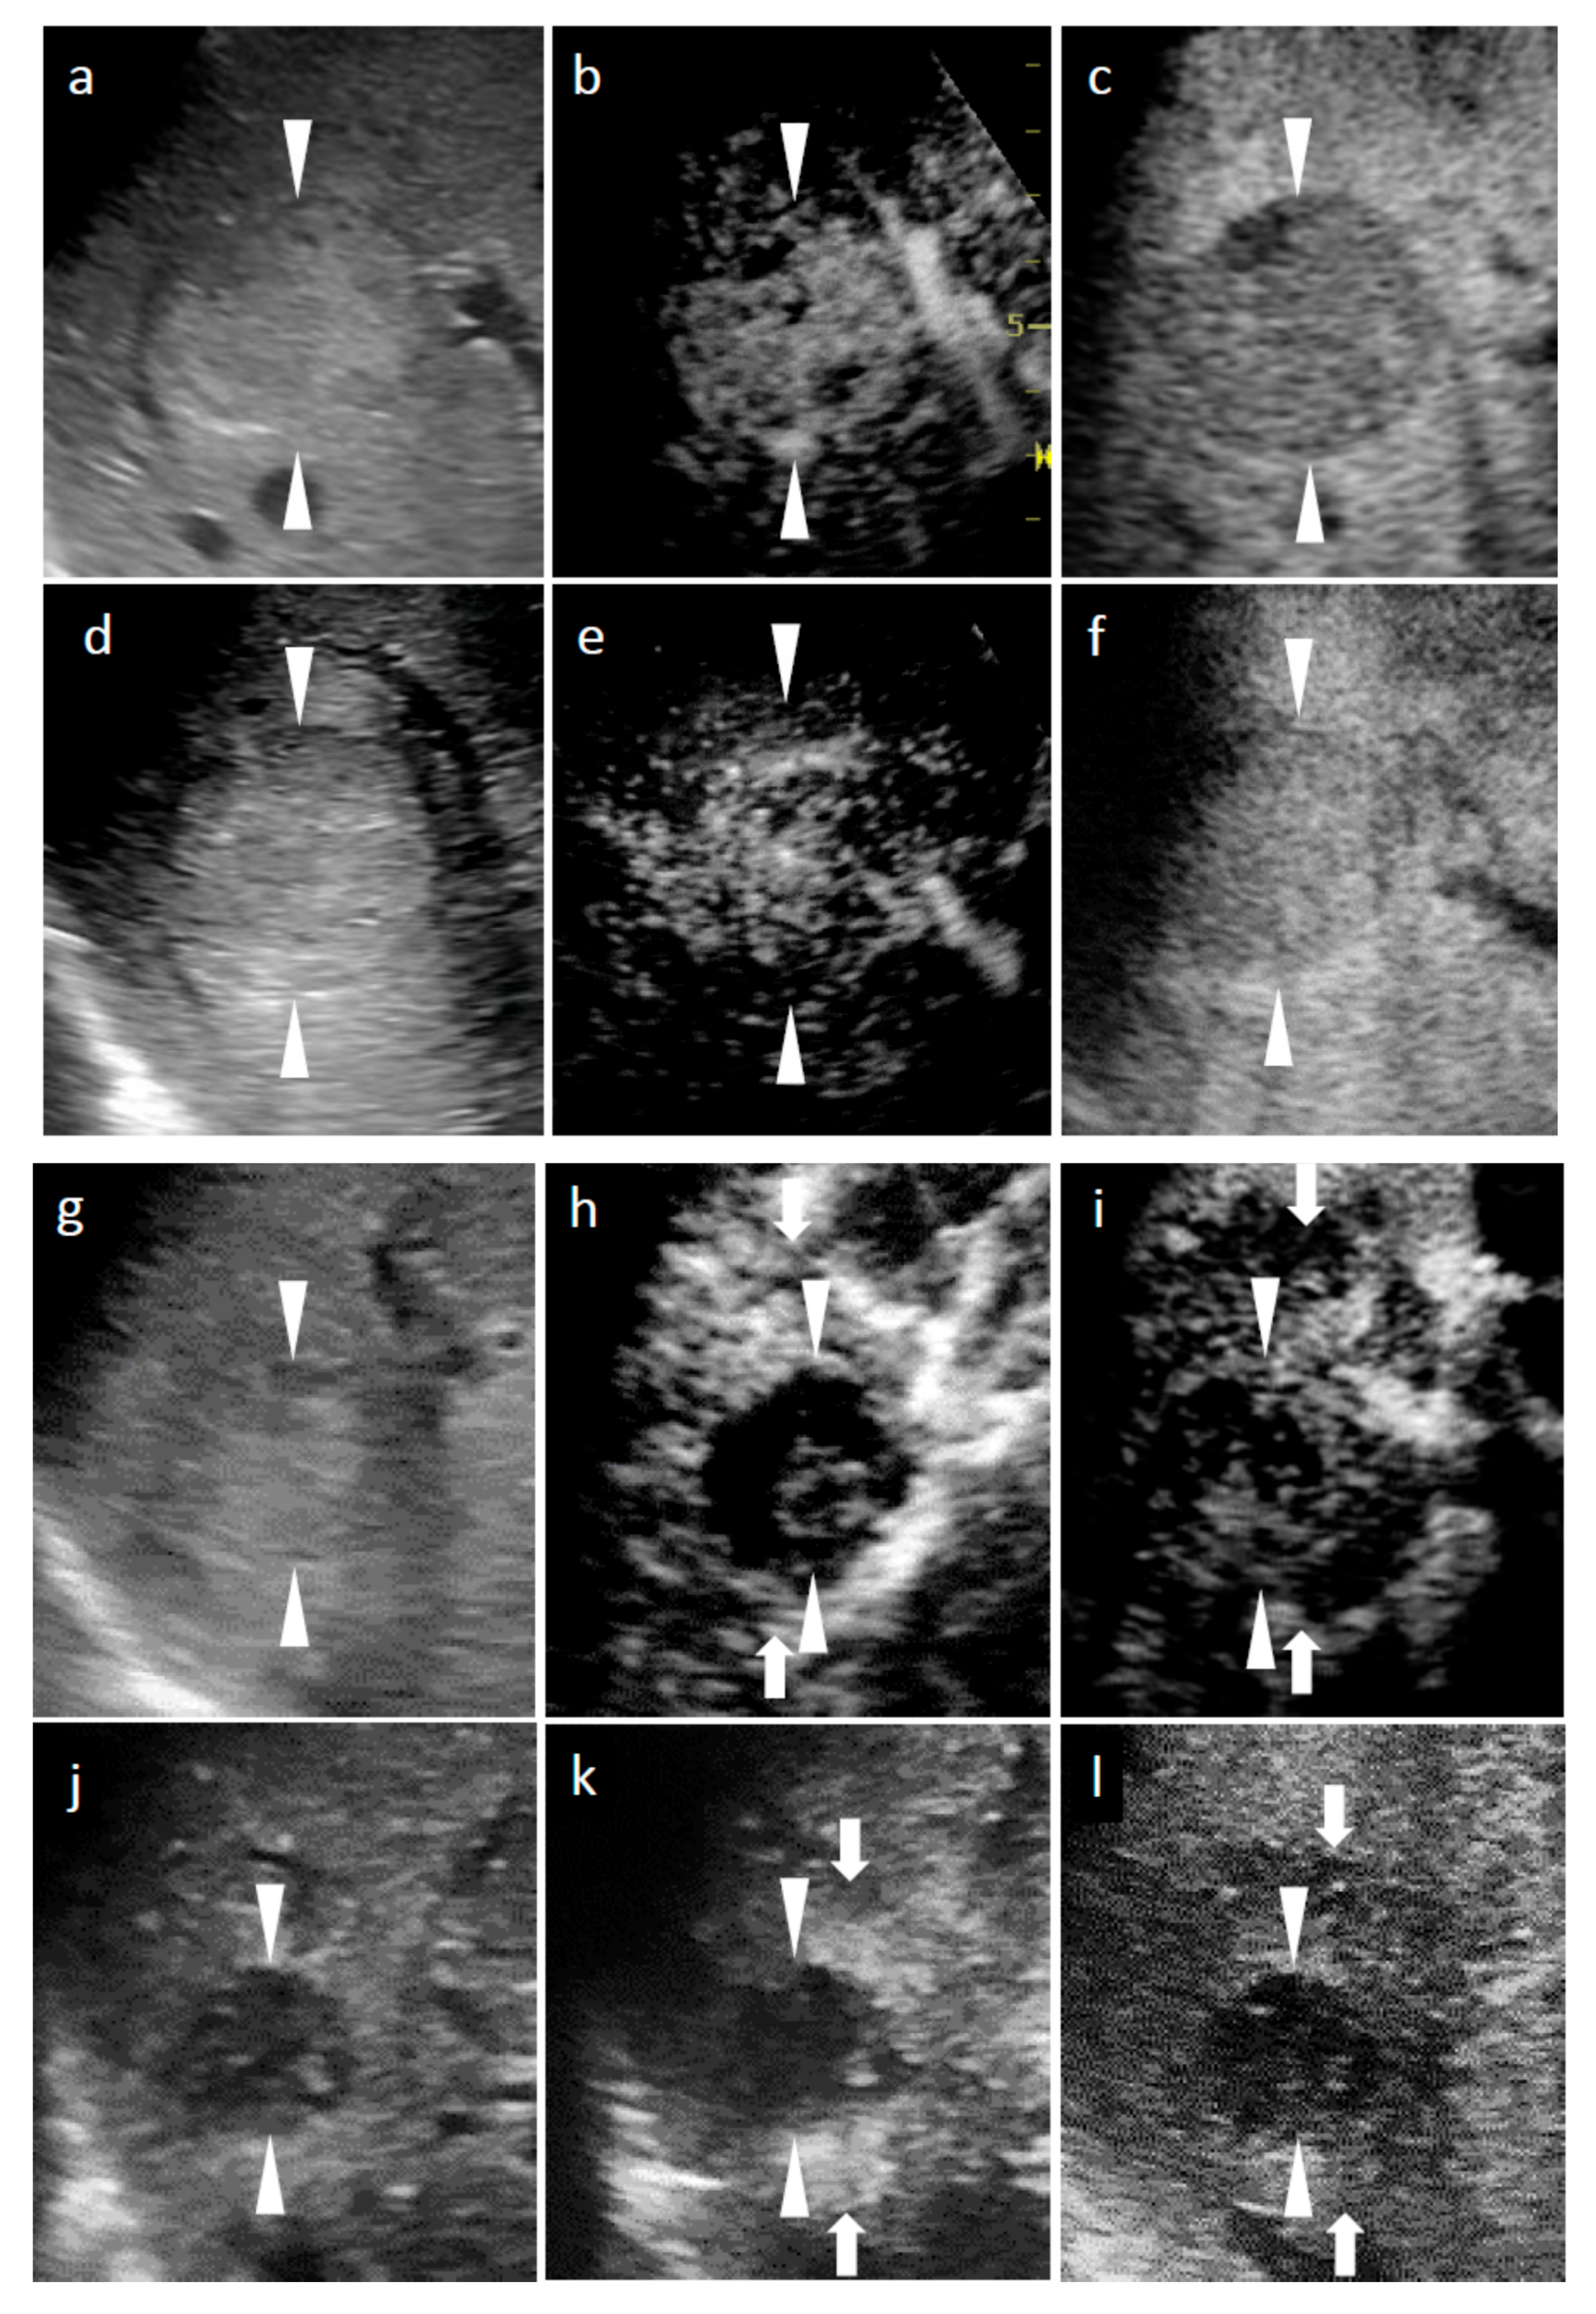

Figure 1.

Grayscale ultrasound (US) and contrast-enhanced US with Sonazoid (SCEUS) images, before and after radiotherapy (RT), for a hepatocellular carcinoma (HCC) lesion (maximum diameter: 38 mm) in segment VIII; evaluated as no local recurrence after RT. The patient was unable to undergo punctuation or surgical resection as they took two antiplatelet drugs during the subsequent 6 months of coronary stenting due to an angina attack. After RT, the patient could not receive contrast-enhanced computed tomography (CT), due to progression of chronic kidney disease. (a–c) Before RT: A hyperechoic lesion was observed using grayscale US (a). This lesion showed hypervascularity during the arterial phase (AP) of SCEUS (b) and hypoechoic (perfusion defect) during the post-vascular phase (PVP) (c). One month after RT (d–f): Grayscale US showed a hyperechoic nodule (d). This lesion showed hypervascularity during AP SCEUS (e) and appeared hypoechoic during the PVP (f) one month after RT. Grayscale US and SCEUS findings obtained after RT showed no remarkable changes, compared with those obtained before RT. Four months after RT (g–i): Grayscale US showed a hyperechoic nodule and a reduction in tumor size (g). AP SCEUS showed decreased vascularity of the HCC lesion and hypervascularity of the surrounding liver parenchyma during the arterial phase (h). Both the HCC lesion and the surrounding liver parenchyma appeared as a perfusion defect during the post-vascular phase (i). Thirteen months after RT (j–l): Grayscale US showed a hypoechoic nodule and a marked reduction in tumor size (j). AP SCEUS showed a disappearance of vascularity of the HCC lesion and slight hypervascularity of the surrounding liver parenchyma (k). Both the HCC lesion and the surrounding liver parenchyma appeared as perfusion defect during the PVP (l). Compared with four months after RT, the size of perfusion defect decreased apparently. Arrowheads indicate the margins of the HCC lesion. Arrows show the margins of irradiated surrounding liver parenchyma.